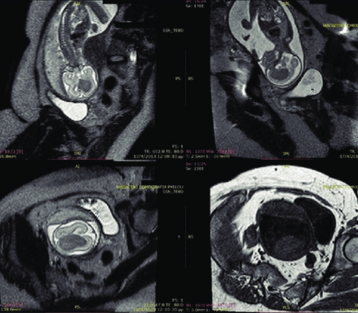

Fetal NeuroSonography

This specialized ultrasound examines the fetal heart in detail, helping to identify congenital heart defects and other cardiac abnormalities.